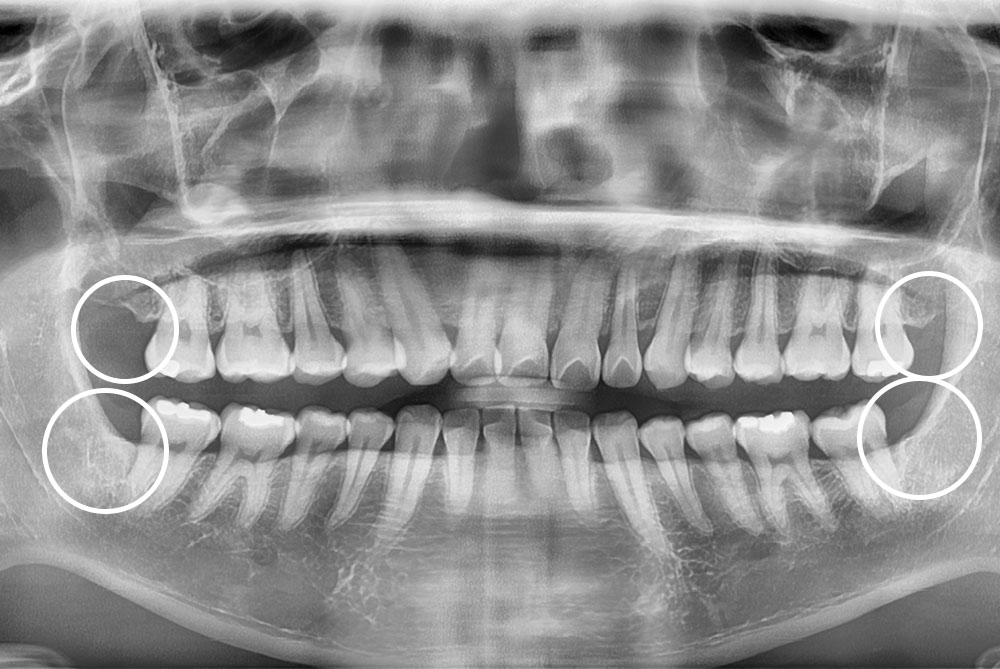

[사랑니] 매복 사랑니 발치

치료후 : 2022-03-18

세종치과는 구강악안면외과학 박사이신 원장님이 발치하는 치과입니다.